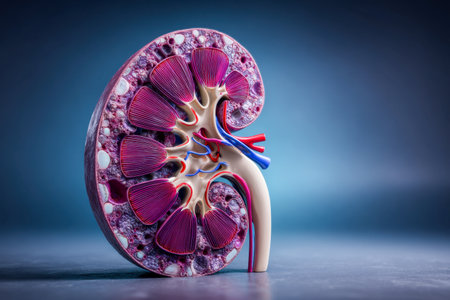

Human kidney cross section on scientific background. 3d illustration

Human kidney cross section

Human kidney cross section on science background. 3d render

Human kidney cross section. 3d illustration

Human kidney cross section.3d render

Human kidney cross section

Kidney disease. Kidney cross section. 3d illustration

An intricate visualization of a human kidney cross-section, highlighting the vibrant layers of the outer cortex, inner medulla, and intertwining blood vessels agains

Kidney disease. Kidney cross section. 3d illustration

Human kidney cross section on scientific background. 3d illustration

Human kidney cross section on scientific background. 3d illustration

Human kidney cross section on scientific background. 3d illustration

Human kidney cross section on scientific background. 3d illustration